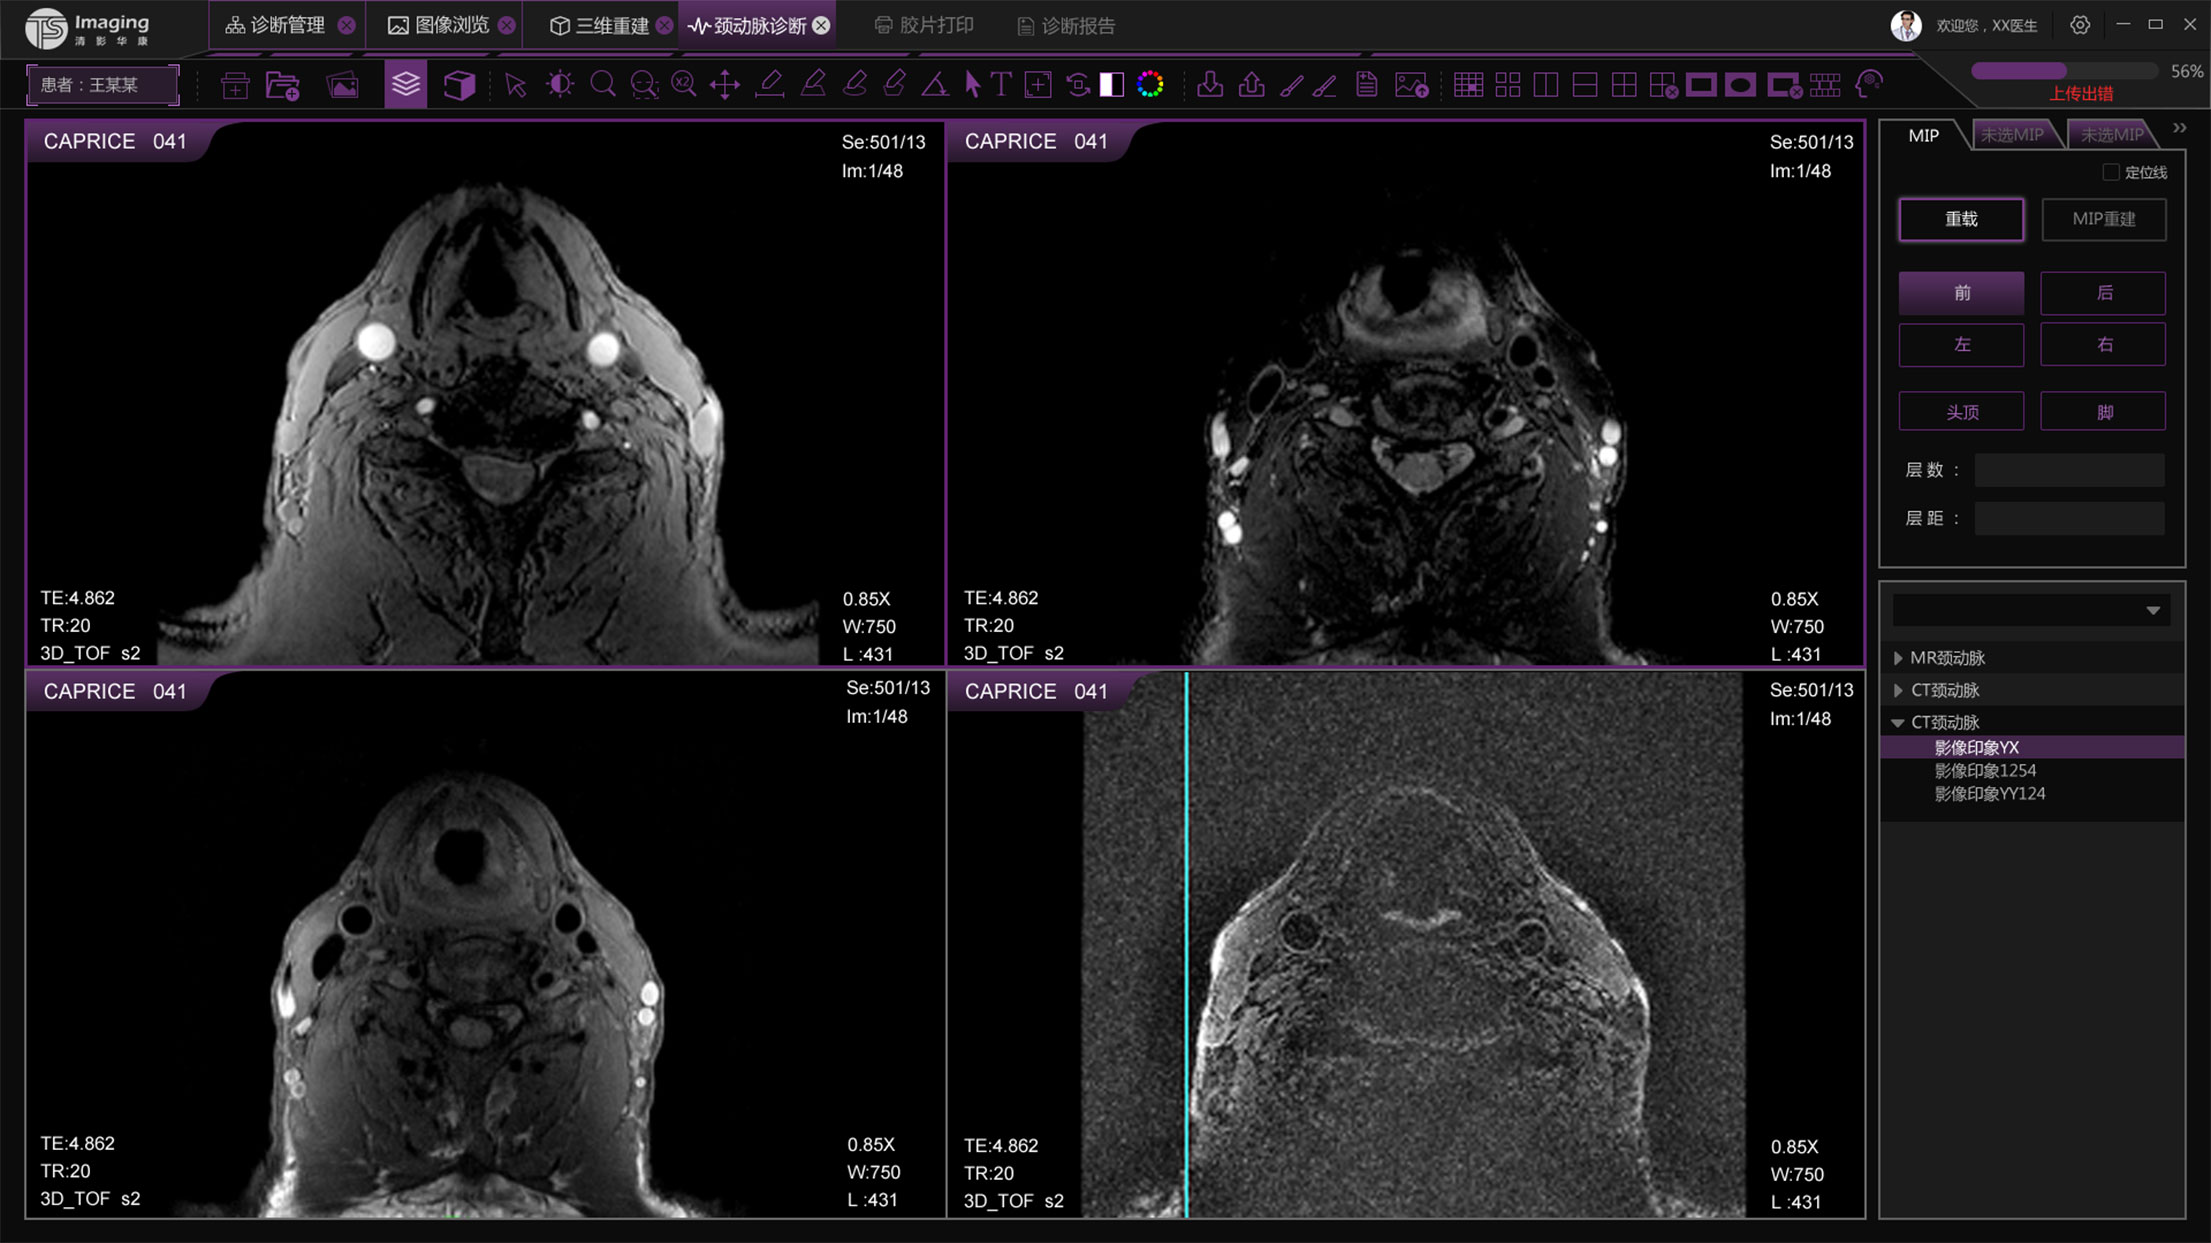

三維重建頁面

三維重建頁面從用戶的使用習(xí)慣上把操作按鈕放到了右側(cè),進(jìn)行交互上的優(yōu)化,上側(cè)的操作按鈕進(jìn)行統(tǒng)一設(shè)計(jì)和現(xiàn)有頁面保持風(fēng)格的統(tǒng)一。左側(cè)的操作區(qū)域可收縮,收起來時(shí)可更好的展示圖像。